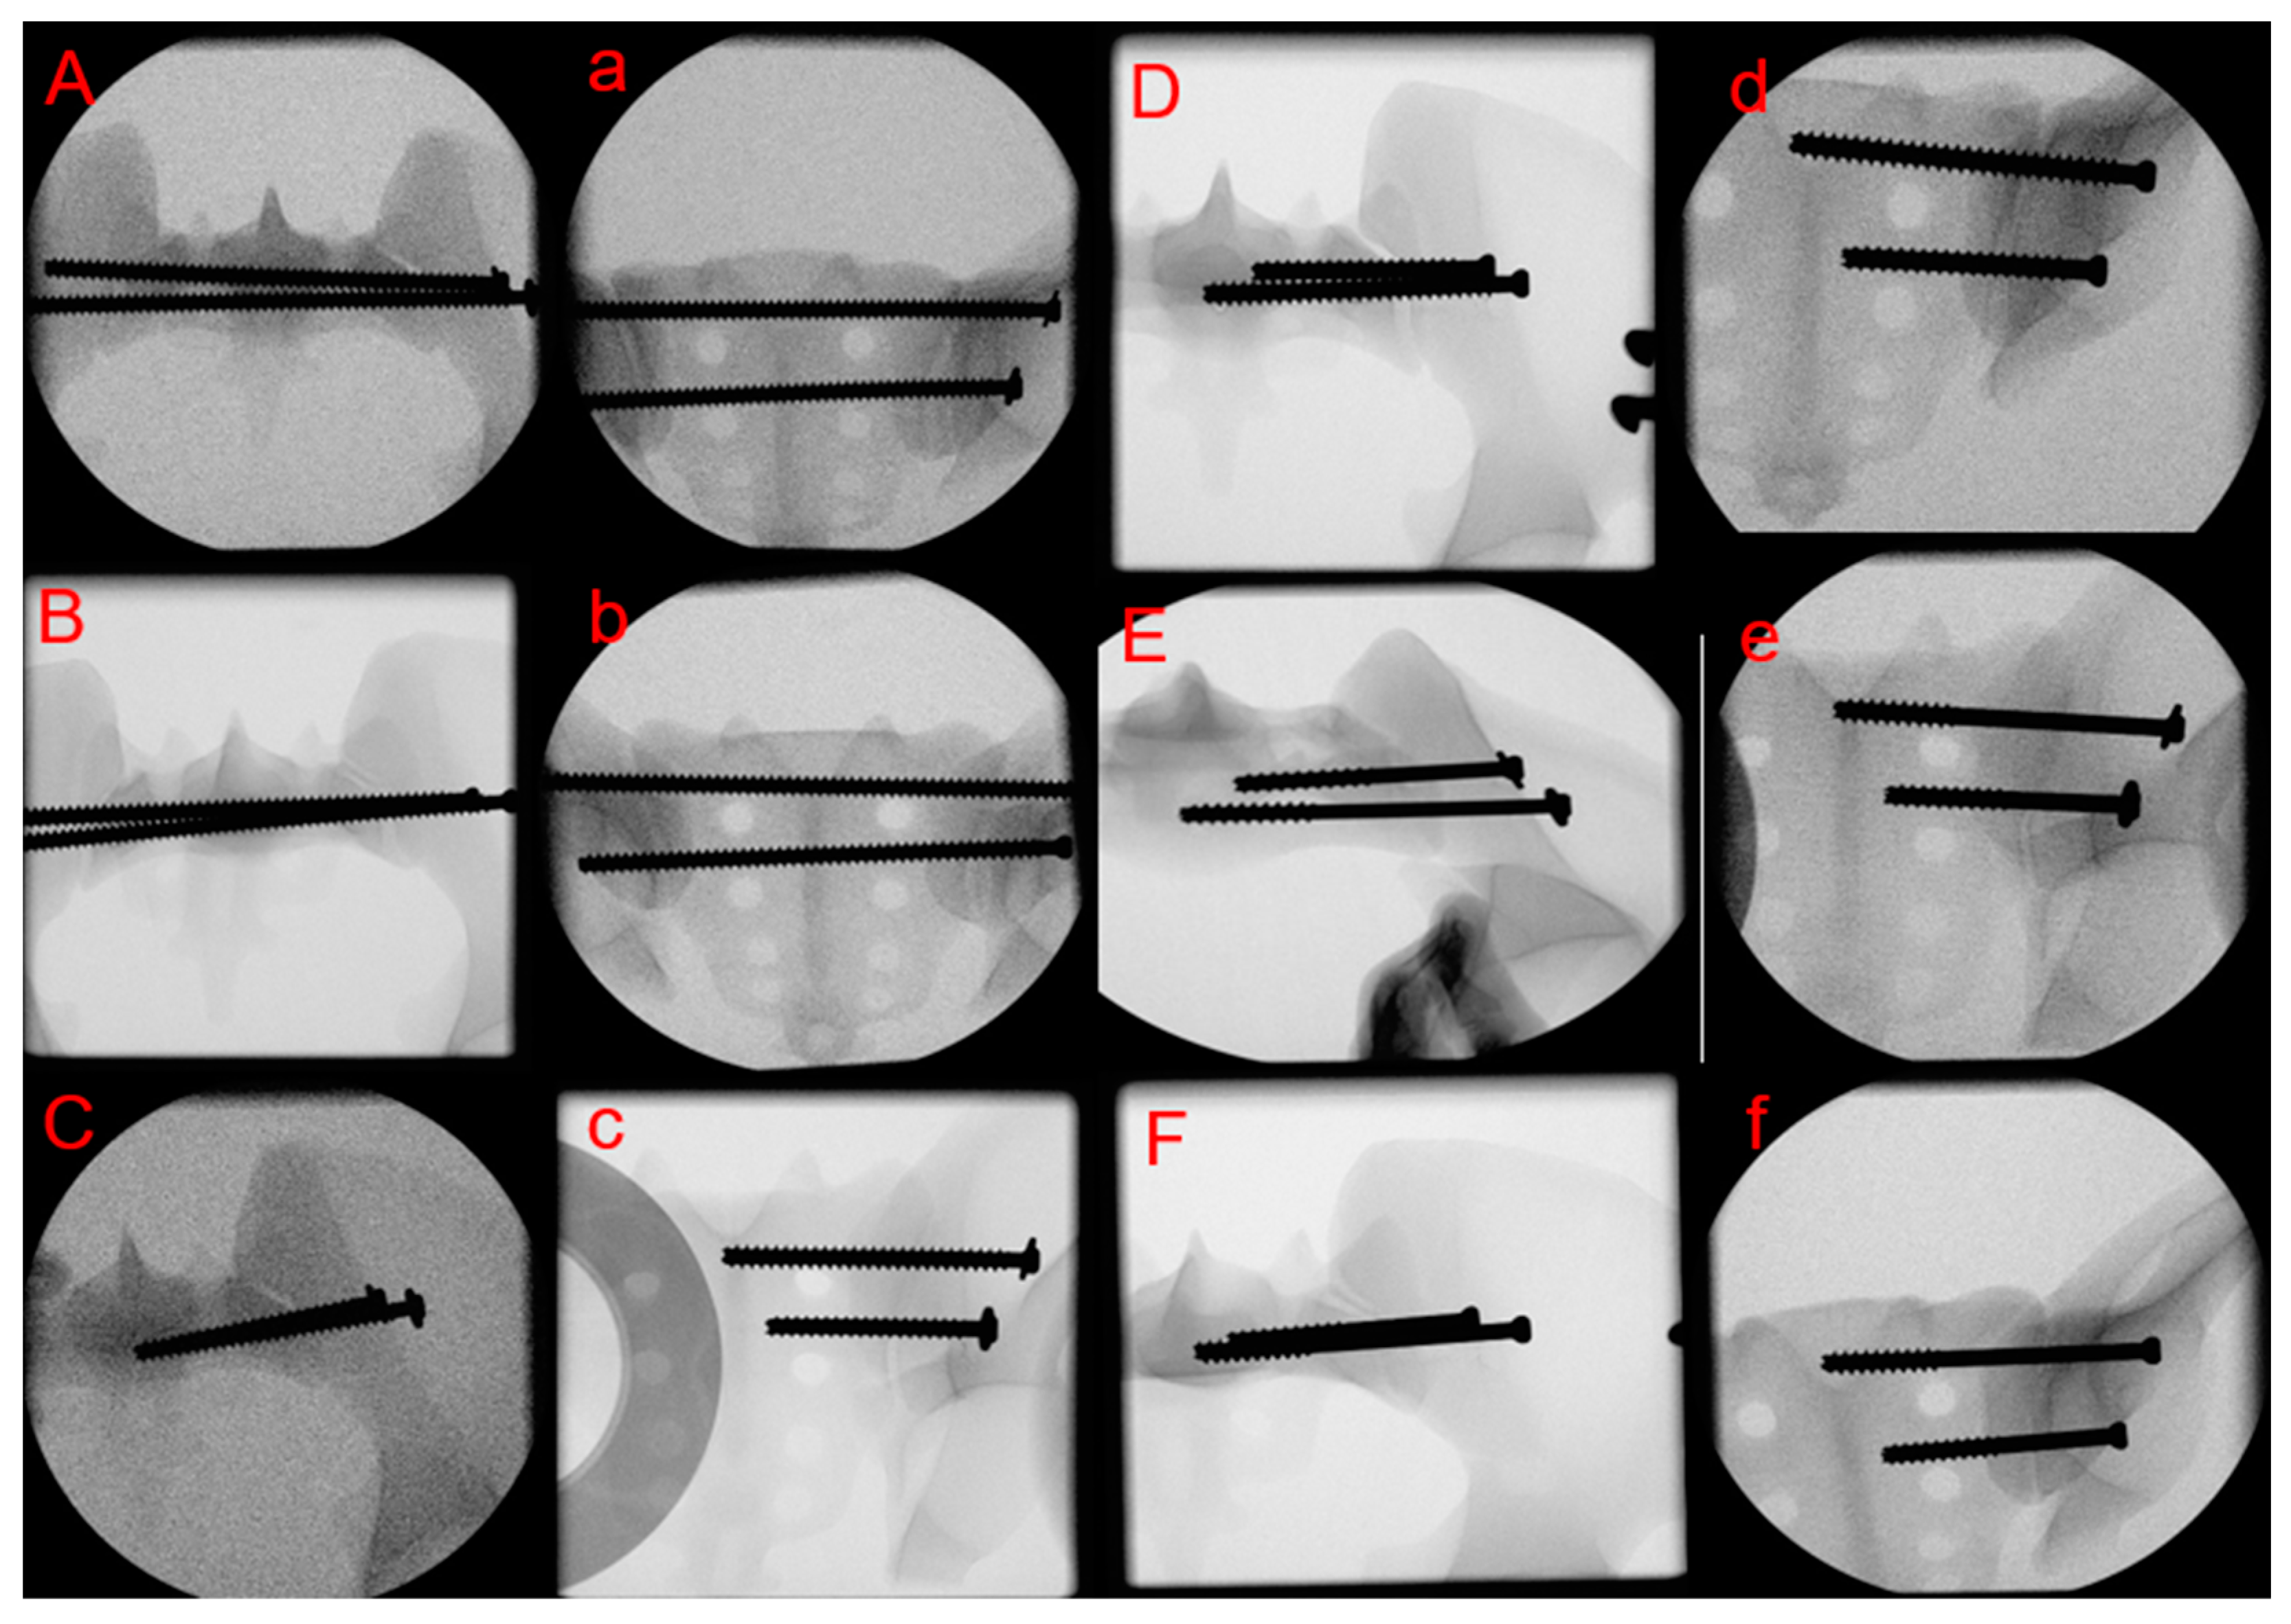

Specimens were stratified into three sets of two groups each for instrumentation as follows (Figure 1):

Equal numbers of three right and three left pelvis sides were utilized in each group (n = 6). The surgical treatment was performed according to the AO principles [22] as follows. After reduction of the SI joints, the self-tapping screws were positioned over a previously placed guidewires perpendicular to the SI joint, entirely within the artificial bone, avoiding any perforations. The insertion of the guidewires was performed with a custom aiming guide, allowing a standardized placement through a single attempt without any perforations or cortical disturbances. First, the S1 SI screw was positioned, followed by the S2 SI screw. The screws ranged to the midline of the sacral vertebra in groups PT w/, PT w/o, FT w/and FT w/o, and to the contralateral ilium cortex in groups TS w/and TS w/o, and were tightened according to the operator’s best judgment. Post instrumentation, true lateral, inlet and outlet x-rays were captured to verify the positioning of the inserted screws (Figure 1).

Figure 1. Inlet (uppercase letters) and outlet (lower case letters) x-rays after instrumentation showing specimens from groups TS w/(A,a), TS w/o (B,b), FT w/(C,c), FT w/o (D,d), PT w/(E,e) and PT w/o (F,f).